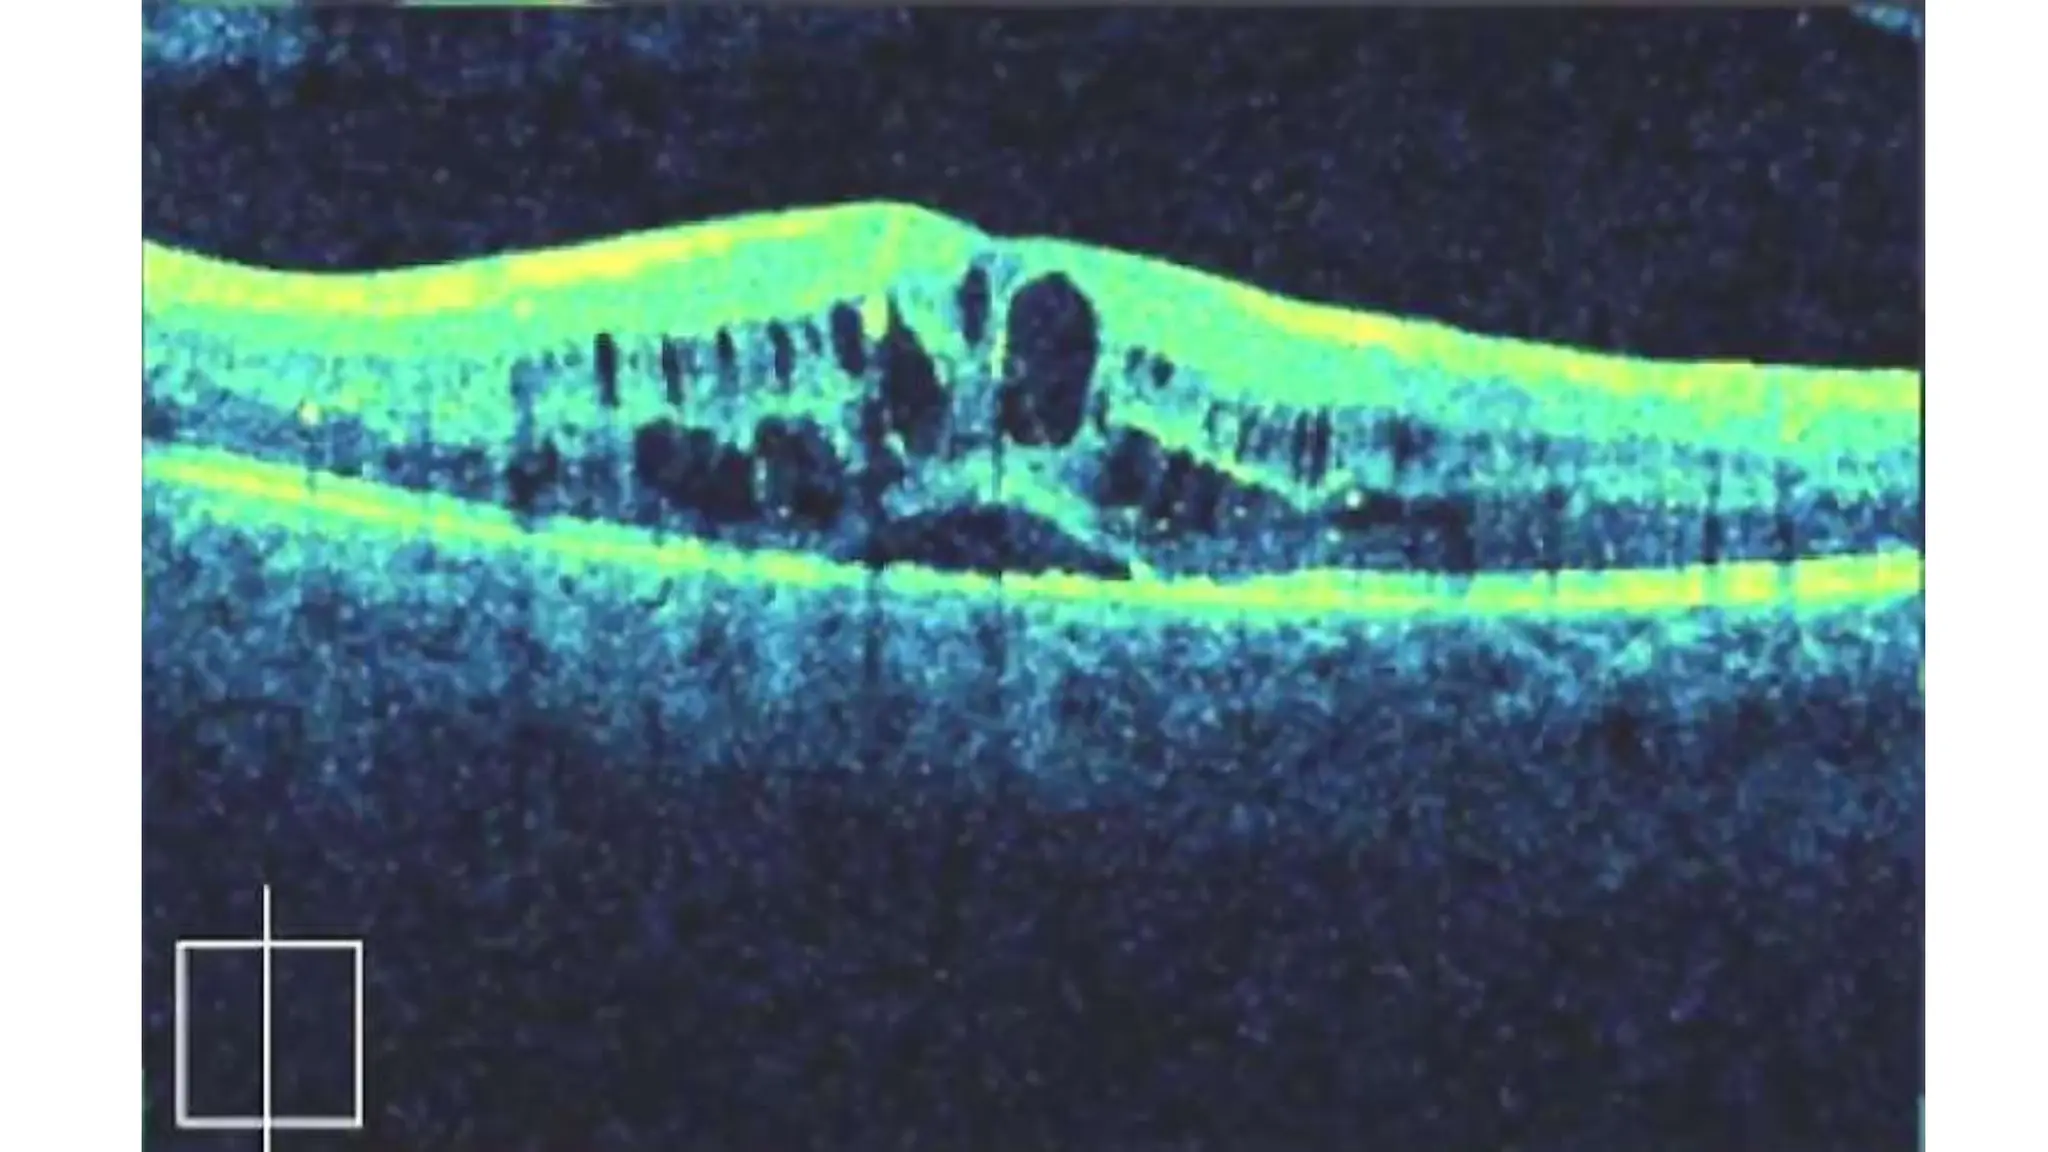

The document discusses various stages of posterior vitreous detachment (PVD) and associated ophthalmological conditions. It highlights the classification of PVD stages, including no PVD, paramacular PVD, and complete PVD, alongside related factors like traction and retinal issues. Key acronyms and terms relevant to diabetic retinopathy and retinal morphology are also mentioned.